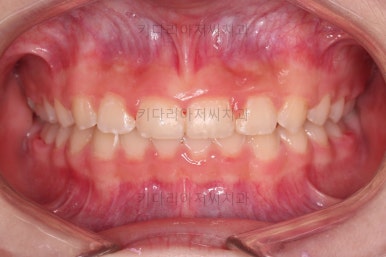

마무리를 해줍니다.

앞니 각도가 매우 좋아졌고요.(옥니 개선) 위아래 앞니가 덮는 정도도 개선이 되었어요.(과개교합, 딥바이트)

엉성했던 어금니 맞물림도 매우 좋아졌어요.(앵글씨 2급 부정교합 개선)

특히 옆라인에서 아래턱이 살아나면서 입매가 매우 예뻐졌어요.

전후사진을 비교해 볼게요.

협조도가 요구되는 장치를 잘 못끼는 바람에 중간에 우여곡절이 있었고, 힘든 과정이 있었지만 비교적 부산교정병원 만족스러운 치료를 할 수 있었어요.

이상 일정부분만 성장교정과 치아교정을 통해 옥니, 과개교합, 앵글씨 2급 부정교합을 치료한 부산교정병원 치료사례였습니다.